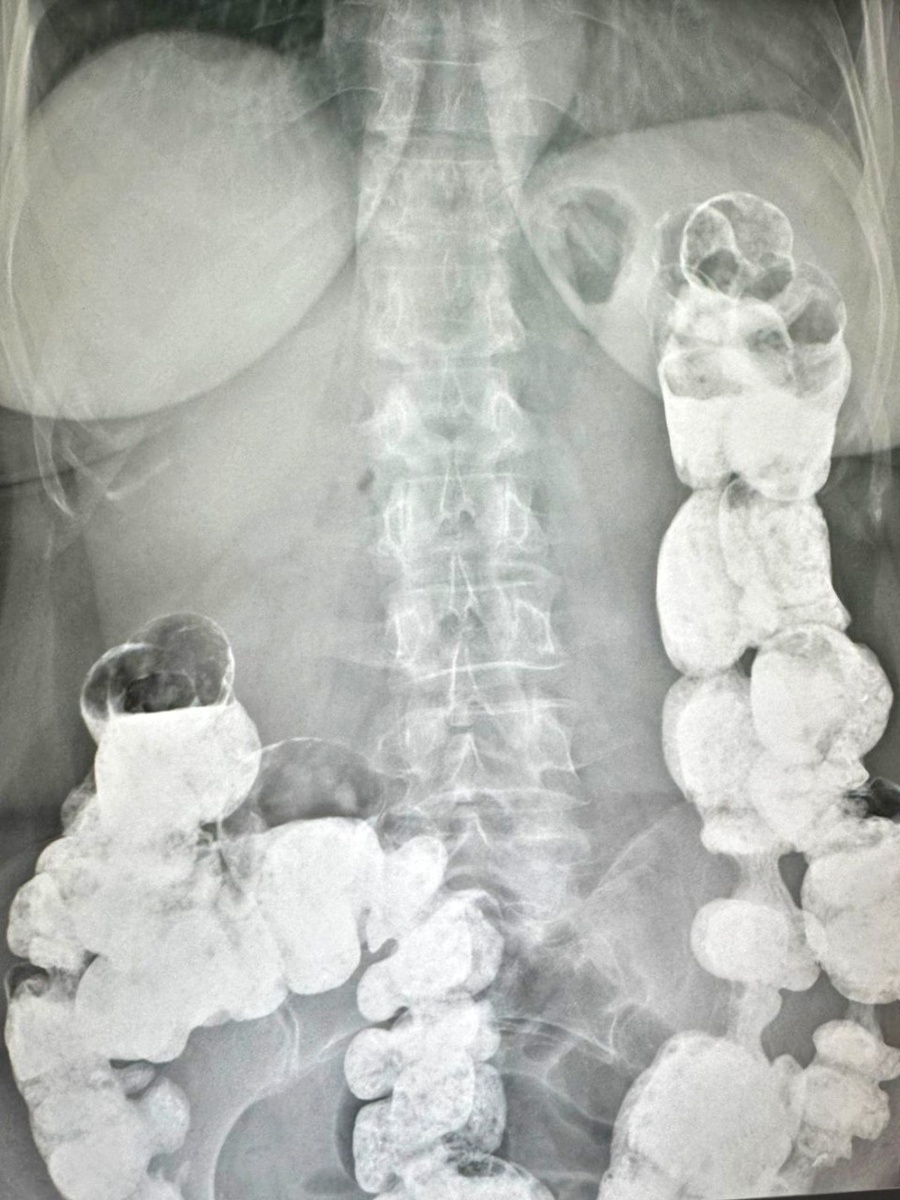

При первичном осмотре гастроэнтеролог А.А.Атаева тщательно собрала анамнез и изучила предоставленную медицинскую документацию. Для уточнения диагноза и определения дальнейшей тактики лечения врач рекомендовала дополнительное обследование, которое ранее пациентке не проводили - рентгенологическое исследование с пассажем бария.

По результатам рентгенологическое исследование пассажа бария по ЖКТ выявлены признаки синдрома Пайра (высокая фиксация селезеночного изгиба) и трансверзоптоз. На основании жалоб, анамнеза и полученных данных при обследовании был установлен диагноз: болезнь Пайра.